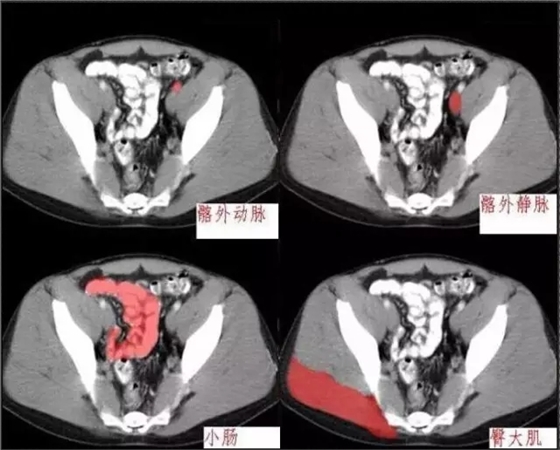

640.webp (4).jpg